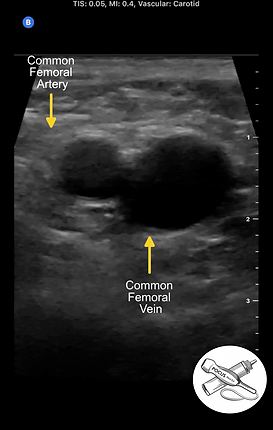

Zone 1: Common Femoral vein to Greater Saphenous vein Junction

The external iliac artery and vein travel down the leg and change names to the common femoral artery and vein after crossing the inguinal ligament. Starting as high as you can get in the inguinal crease, identify the common femoral vessels. They are usually large and running parallel. Artery will be lateral, vein medial. ​​

Sweep the probe down toward the feet, compressing every 1 to 2 centimeters until the Greater Saphenous vein is seen exiting the Common Femoral vein.